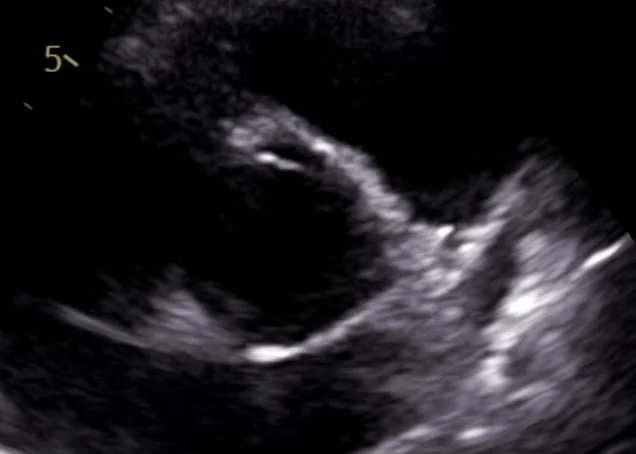

It's pretty hard to get definitive imagery for bicuspid valves, which are deeply nested within the body. The standard practice today is to use echocardiograms, which are essentially ultrasounds pointed at the heart. 2D echocardiograms give us 2D 'cross-sections' of the heart, at a depth defined by the tool's controls; watching this cross-section over time allows one to see the movement of the valve over the plane, and hence approximate the rough structure of said valve. Here's a quick GIF of one of my 2D echoes from 2021: